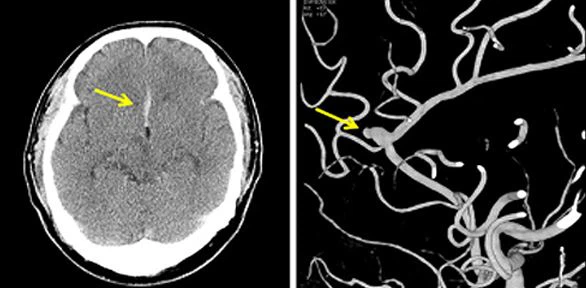

특히 뇌동맥류가 두 번 이상 터질 경우에는 70~80%에서 심한 후유증을 남기거나 생명을 잃게 됩니다. 뇌동맥류가 터지기 전에 CT 조영 촬영(CTA)이나 MRA를 촬영하면 약 95%이상에서 뇌동맥류를 발견할 수 있습니다. 치료 방법을 결정하기 위한 가장 중요한 검사는 뇌혈관 촬영인데 1-2일 정도 입원이 필요합니다.